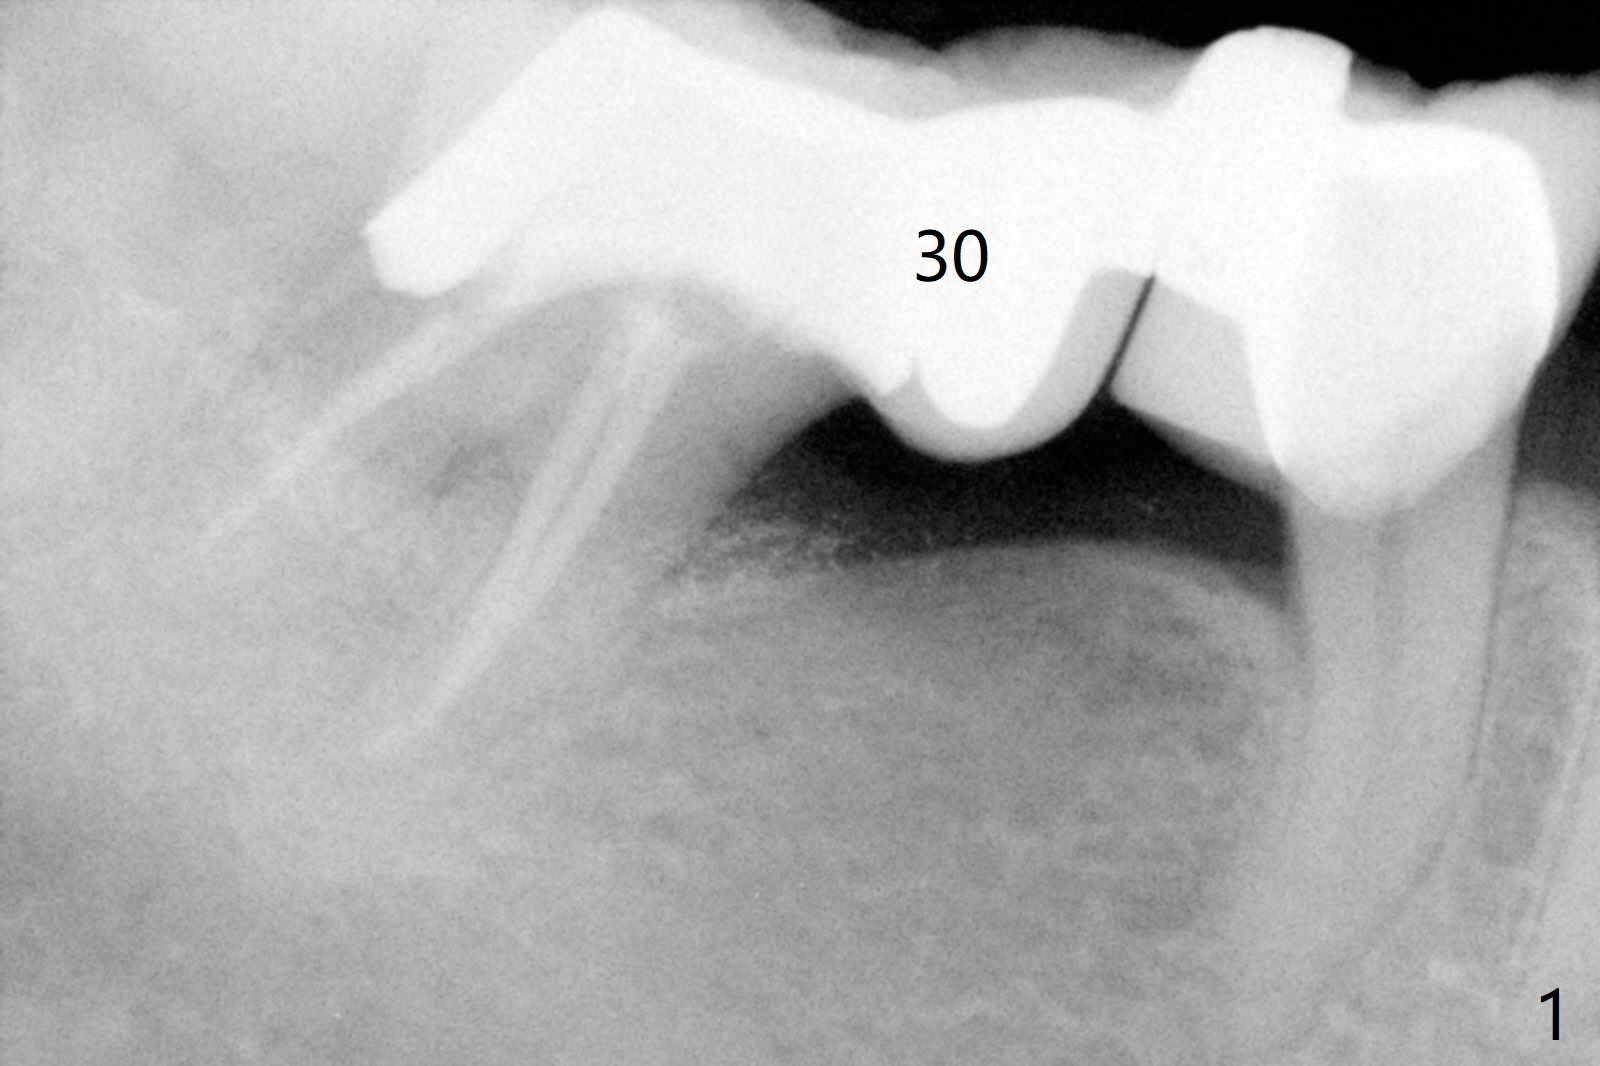

A 60-year-old man has food impaction under the pontic of the lower right FPD (Fig.1-3: #30). The ridge should be thin, since the bone density in the edentulous area is low. The mesiodistal width is also limited. A 1- or 2-piece implant (3.5x8.5 mm, Fig.4 (CT coronal section)) is expected. Use wheel to section the ridge vertically and Rongeur to remove the ridge. Grind the latter for graft. Place a wide abutment to increase the width of the pontic site to reduce food trap.